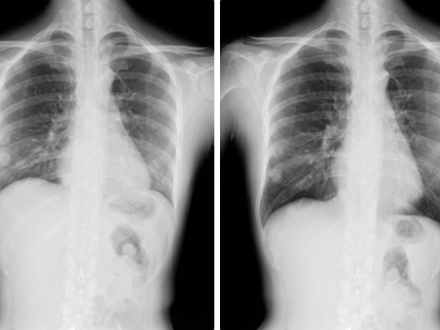

Wayne, NJ, May 23, 2024 – In a landmark study, the latest in technology innovation by Konica Minolta Healthcare was used to develop a machine-learning-based analysis of X-ray imaging that automatically quantifies lung function data. This AI-powered technique provides a reliable alternative to pulmonary function tests (PFTs), which have limited assessment capabilities and can be difficult for some patients with pulmonary disorders to complete. Researchers at the Icahn School of Medicine at Mount Sinai ("Icahn Mount Sinai") used Dynamic Digital Radiography (DDR) data, an X-ray imaging technology developed by Konica Minolta, to create their AI-powered technique that analyzes lung function. The researchers found their AI-based software provides additional quantitative data that may be useful in differentiating pulmonary disorders and a possible marker for treatment escalation, according to findings published online in press in the journal CHEST Pulmonary.

DDR is a next-generation X-ray imaging technique that enables visualization of anatomy in motion. PFTs and chest radiography are both typically utilized for the evaluation of pulmonary disorders and respiratory function; however, these tools offer a static assessment. Also, PFTs provide an assessment without correlating anatomical information and can be difficult for some patients to perform. The addition of DDR provides visualization of dynamic lung function and diaphragm motion, is easy to obtain during normal breathing patterns, and enables a functional evaluation of the interaction between the lungs, diaphragm and heart during a breathing cycle.

The researchers created an analysis pipeline using a convolutional neural network (CNN) to quantify DDR data in lung areas during normal respiration, maximal inhalations and exhalations. They compared PFT to the DDR-based PFT across multiple data points and found a strong correlation between the two technologies. They also reported the automated DDR pipeline facilitates tracking anatomy, providing lung area-time and flow-area loops analogous to PFT volume-time and flow-volume loops. The researchers said DDR can depict diaphragm motion and respiratory muscle synchrony, making it feasible for longitudinal studies, as a screening tool for pulmonary physiology workup and as a treatment aid, particularly in emergency settings or where a PFT is not feasible or available. The AI-based software developed by the authors for the study is available as an open-source code on GitHub.